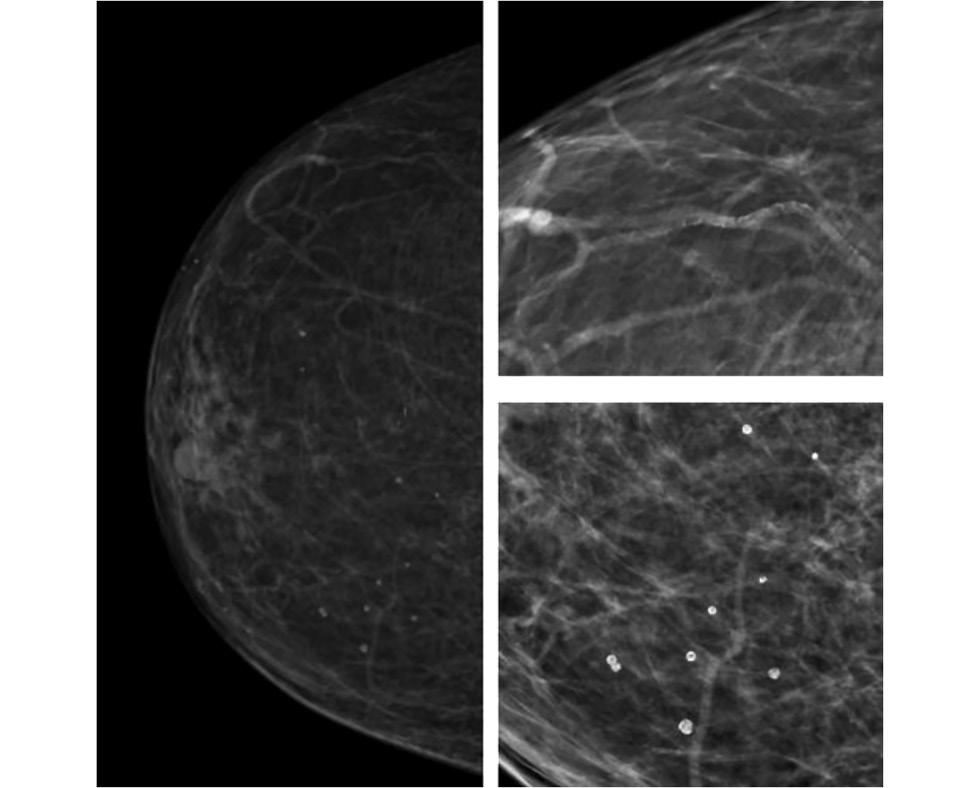

Radiographic markers of cardiovascular risk based on digital mammograms: a cross-sectional study

Abstract

BACKGROUND: Studies have demonstrated an association between cardiovascular risk and mammographic density and breast arterial calcification. However, their combined impact remains poorly understood.

AIM: This study aimed to evaluate the correlation between mammographic density, breast artery calcification, and cardiovascular risk category in asymptomatic women aged ≥40 years.

METHODS: This retrospective, single-center, selective study included women who underwent preventive screening mammography at the University Clinic of Lomonosov Moscow State University between 2019 and 2023. The Systematic Coronary Risk Evaluation 2 was used to determine cardiovascular risk categories. A radiologist evaluated mammograms at a workstation to obtain data on mammographic density and glandular calcifications. The data were analyzed using a machine learning technique called Uniform Manifold Approximation and Projection. Univariate logistic regression was employed to calculate odds ratios and 95% confidence intervals. The reference group included mammograms showing high breast density and no calcifications. The odds ratio for each selected group is presented relative to the reference. The contingency tables were assessed using Pearson’s chi-squared (χ2) test. The significance level for all tested hypotheses was set at 0.05.

RESULTS: The mammograms of 1030 women aged 40–89 years were evaluated. Based on the study results, eight groups (G7–G0) were formed, depending on combinations of the following criteria: high or low glandular density, presence or absence of vascular and nonvascular calcification, and extent of calcification. Women with low mammographic density and vascular calcifications in more than one quadrant were found to have a >75% likelihood of high or extremely high cardiovascular risk. The probability exceeded 90% for a combination of vascular and nonvascular calcifications in two or more quadrants.

CONCLUSION: A correlation was found between calcifications, mammographic density, and cardiovascular risk category.

398-413